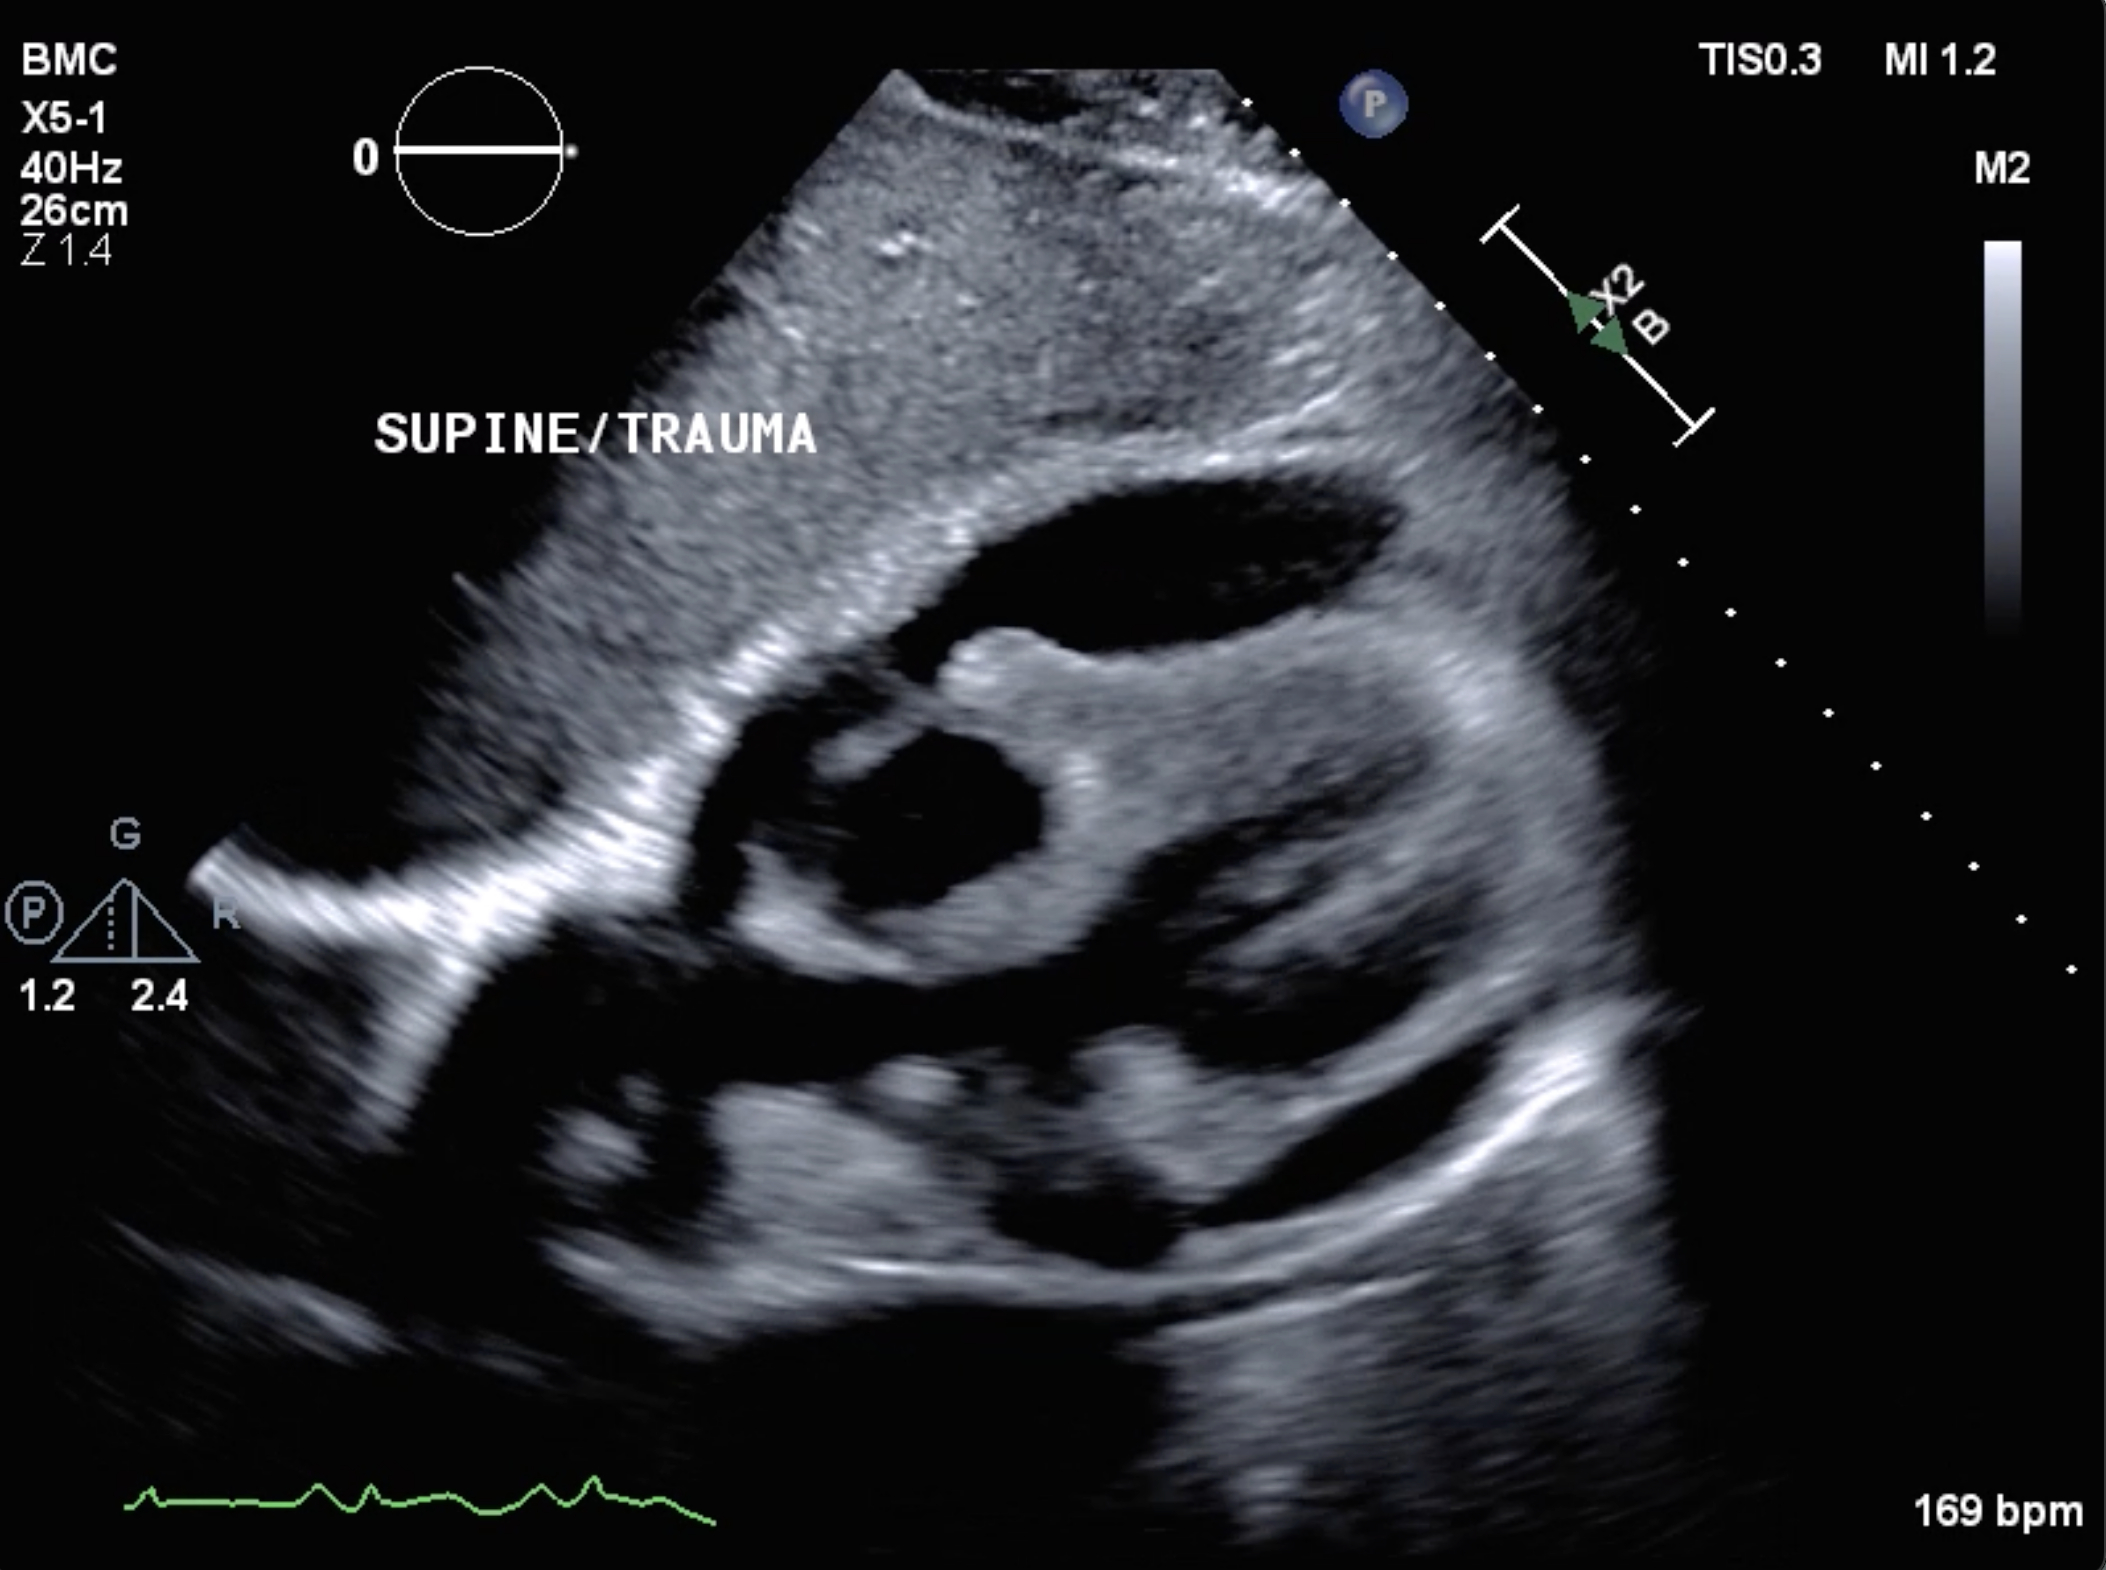

Purulent Pericarditis Leading to Cardiac Tamponade and Constrictive Physiology

Case Summary: A middle-aged woman presented with chest pain. Initial imaging showed no evidence of pneumonia or pericardial effusion. A repeat echocardiogram after approximately 16 hours demonstrated the development of cardiac tamponade and obstructive shock. Emergent pericardiocentesis yielded purulent fluid, which grew Streptococcus pneumoniae. Despite hemodynamic improvement, she subsequently developed CP, which was diagnosed with cardiac catheterization and cardiac magnetic resonance (CMR).

Discussion: This case illustrates an uncommon and critical presentation of purulent pericarditis in a previously healthy adult without initial evidence of pneumonia or an identifiable infectious source. The patient’s rapid progression to cardiac tamponade and obstructive shock highlights the importance of early recognition, timely pericardial drainage, and targeted antimicrobial therapy. Additionally, the classic signs of CP were seen just days after the development of pericardial disease. Cardiac catheterization is the gold standard diagnostic tool because enhanced ventricular interdependence by analysis of the left ventricular and right ventricular pressure contours during the respiratory cycle is highly sensitive and specific. However, CMR offers a non-invasive diagnostic adjunct by revealing pericardial thickness, pericardial contrast enhancement, and ventricular coupling during real-time cine imaging. This complementary information can help guide treatment decisions on medical therapy versus surgical intervention.